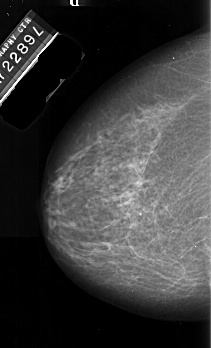

A_1015_1.LEFT_MLO

ics_version 1.0

filename A-1015-1

DATE_OF_STUDY 22 5 1989

PATIENT_AGE 69

FILM_TYPE REGULAR

DENSITY 2

DATE_DIGITIZED 5 1 1998

DIGITIZER DBA 21

LEFT_MLO LINES 6526 PIXELS_PER_LINE 3346 BITS_PER_PIXEL 16 RESOLUTION 42 NON_OVERLAY